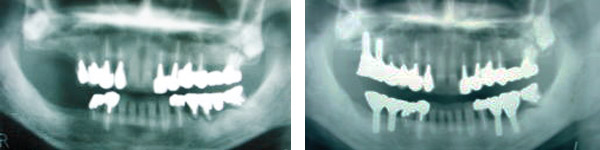

治療前(写真左)と治療後(写真右)。